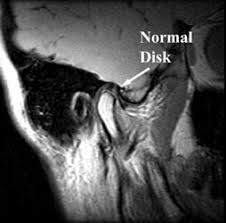

- التصوير بالرنين المغناطيسي – MRI: يعمل على إظهار الأنسجة الرقيقة كأنسجة مفاصل الفك للتأكد من وجودها في مكانها الطبيعي عند حركة الفك في أي اتجاه

صورة رنين مغناطيسي لمفصل سليم